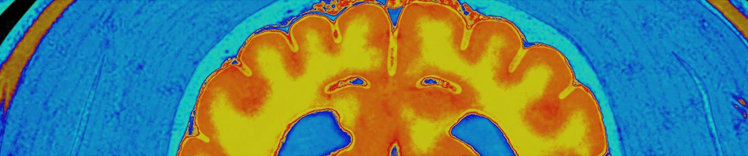

神经元质量和脑 MRI

大脑衰老时的变化

衰老时大脑中相关的生理变化包括:

- 某些部位组织萎缩(缩减)

- 脑室体积增大

- 神经元和突触丧失以及新生神经元减少

- 异常蛋白质积聚